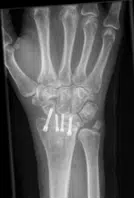

Häufig sind zur langfristigen Schmerzverbesserung nur teilversteifende Operationen, oder aber die Entfernung einzelner Handwurzelknochen sinnvoll. Nach derartigen Operationen ist die Gesamtbeweglichkeit des Handgelenkes zwar reduziert – mit 30° Streckung und 30° Beugung- dies ist jedoch im Alltag meist ausreichend und das bei einer deutlichen Reduktion der vormalig vorhandenen Schmerzen.

In ausgewählten Fällen kann auch ein prothetischer Gelenkersatz am Handgelenk vorgenommen werden, als letzte Möglichkeit bleibt zur Schmerzausschaltung die Komplettversteifung des Handgelenks.